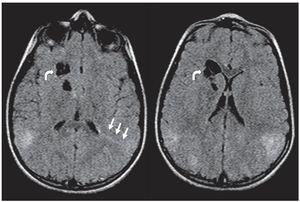

En la TC son isodensos con respecto a la sustancia blanca, pero en pacientes mayores pueden calcificarse y ser hiperdensos (fig. 1). Si bien los hamartomas se calcifican progresivamente durante las dos primeras décadas de la vida, difícilmente se encuentre un nódulo calcificado en menores de 1 año. En cuanto a su ubicación, los hamartomas se proyectan hacia los ventrículos laterales o están «sumergidos» en los márgenes de los núcleos caudados. En el 95% de los casos, son bilaterales.

Figura 1. Tomografía computada, corte axial, de un paciente de sexo masculino de 1 año de edad. Se identifican imágenes nodulillares hiperdensas y calcificadas, de localización subependimaria, compatibles con hamartomas subependimarios, e imágenes hipo densas corticales compatibles con túberes.

En la RM los hamartomas subependimarios de los recién nacidos son ligeramente hiperintensos en ponderación T1 con respecto a la sustancia blanca y de intensidad heterogénea en ponderación T2, debido a la hipomielinización de la sustancia blanca. A medida que ocurre la mielinización, los nódulos se tornan isointensos en ponderación T1 y T2 en relación con esta. Si se calcifican, son marcadamente hipointensos en secuencias de eco de gradiente (GRE). La captación poscontraste paramagnético es variable (fig. 2), siendo más frecuente la ausencia de realce1,2.